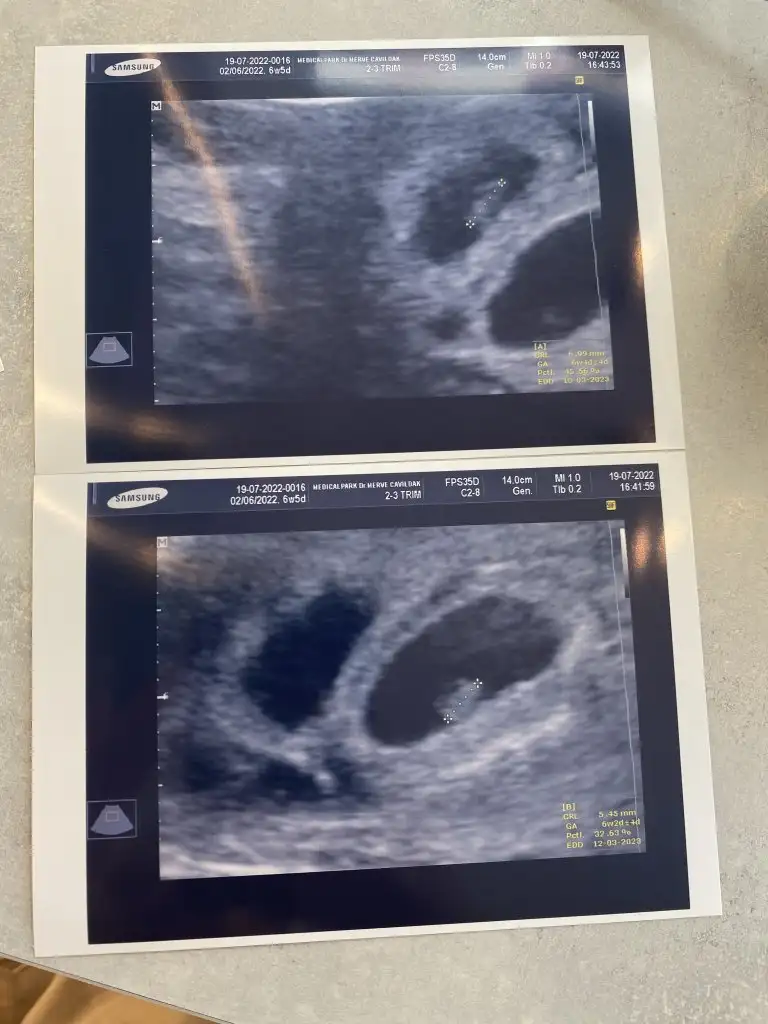

Sağol canım sorduğun için benimkiler iki tane çıktığından beri şokumu atamıyorum kalp atışını duyduk bebişler 2 gün arayla olmuşlarolmadibe sen ne durumdasın cnm

Yaaaa çok iyi maşallah . Rabbimin taktiri işte bak. Sen istersin o iki tane verir. Sağlıcakla kucağına alırsın inşallah cnmSağol canım sorduğun için benimkiler iki tane çıktığından beri şokumu atamıyorum kalp atışını duyduk bebişler 2 gün arayla olmuşlarEki Görüntüle 3100277

Kullanıcı adın olmadıbeydi ama bebeklerin sana oldu be olduuuy dediSağol canım sorduğun için benimkiler iki tane çıktığından beri şokumu atamıyorum kalp atışını duyduk bebişler 2 gün arayla olmuşlarEki Görüntüle 3100277

Düşük tehlikem varmış, kanamam oluyor başka bi sıkıntım da yok Allaha şükür hafif mide bulantım dışındaİlk hamişimiz bebişiniz nasıl başka bir sayfada kanama ile ilgili soru sorduğunuzu gördüm inşallah sıkıntı yoktursultansym